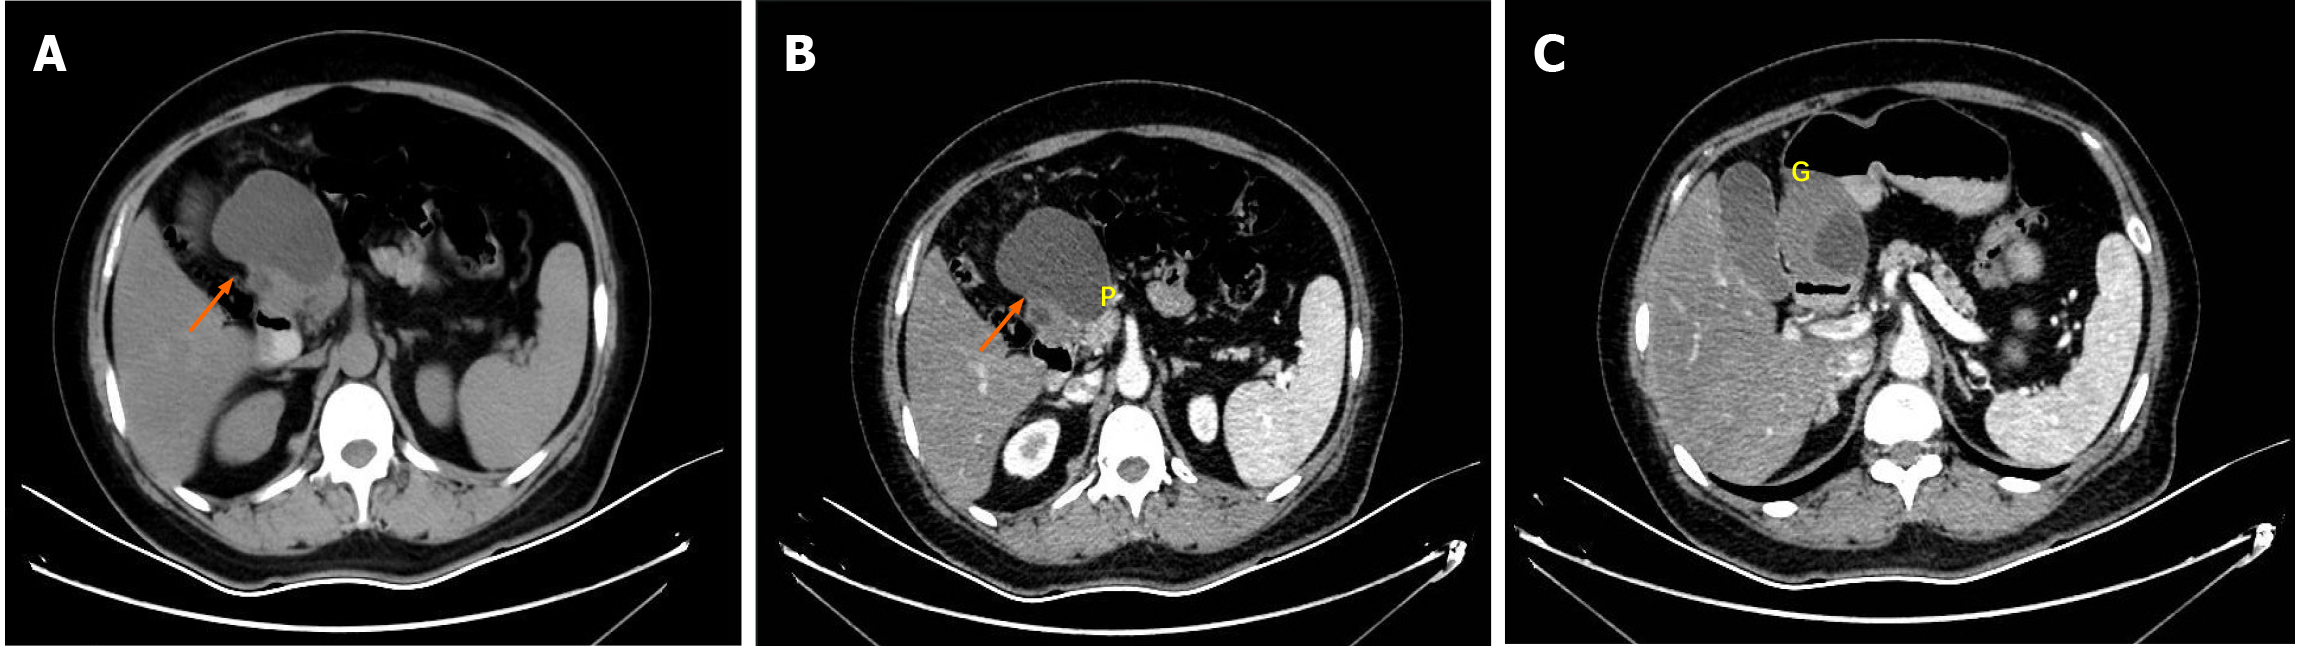

Contrast-enhanced abdominal computed tomography (CT) identified a cystic lesion in the right upper abdomen (Figure 1). This showed close anatomical relationships with both the pancreatic head and the greater curvature of the gastric antrum. An initial radiological assessment favored a benign pathology, with differential diagnoses including intestinal duplication and pancreatic cystadenoma. The subsequent pancreatic protocol magnetic resonance imaging with diffusion-weighted imaging (Figure 2) confirmed these findings but showed no evidence of malignancy.

An upper endoscopy revealed the following: (1) A large, soft submucosal lesion involving the pylorus and greater curvature of the gastric antrum, with preserved luminal patency; (2) An ulcerated lesion at the duodenal bulb-descending junction, with luminal narrowing and raised margins (Figure 3); and (3) Endoscopic ultrasonography (EUS) identified a 7 cm × 4.8 cm mixed cystic-solid mass with clear demarcation from the adjacent organs but a loss of interface with the fourth layer of the gastric wall (Figure 4).